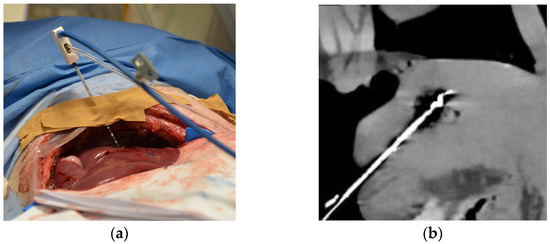

Four MWAs were performed on normal liver tissue in a ventilated 6-month-old female domestic pig under general anesthesia. The animal was housed in the central animal husbandry of the Charité with compliance to 2010/63/EU-directives and recommendation of the GM-Solas (Society for Laboratory Animal Science, Freiburg, Germany) for pig husbandry. The experiments were conducted in 2020 using the latest CT technology as a proof of concept for further clinical trials. The porcine liver is similar to human liver parenchyma, and the artifacts due to respiration and heart action serve as a realistic model. The liver was exposed in a sterile environment to ensure better access to the organ with the ablation and temperature probes (Figure 1a). For each of the three ablations successfully performed, the MWA probe (AveCure, MedWaves Incorporated, San Diego, CA, USA) power was set to 100 W. One CTT dataset of the liver was acquired without thermoablation. The probe was placed in porcine liver for the respective ablation in such a way that there was sufficient distance to the other ablation areas. During each MWA, 20 spectral acquisitions were acquired without table movement using 16 cm detector coverage (Canon Aquilion ONE Prism; Canon Medical Systems, Otawara, Japan). Scan parameters: rapid kVp switching between 80 and 135 kVp, 1 s rotation time, 500 mA tube current. The first scan was acquired right at the beginning of the ablation, and each further scan at 30 s intervals throughout the 5 min of ablation. Maximum temperature was reached when the 10th scan was acquired (Tmax), and the probe cooled down during the remaining session (Figure 1b). Another 10 CT scans after the energy gift of the MWA were acquired every 60 s, covering the postablation phase. The animal was euthanized at the end of the experiment, and the liver was removed for histopathological assessment.

Figure 1.

Experimental setup of computed tomography (CT)-based thermography (CCT): (a) Intraoperative photograph showing the animal under general anesthesia with the liver exposed and the microwave ablation (MWA) probe inserted; (b) CT image showing inserted MWA probe in the liver at the end of heating phase reaching maximum temperature (Tmax) before cooling down. In the same axis with a clear representation of the ablation probe and zone, the images for the rating were set.

All images were anonymized for blinded assessment and displayed with settings, ensuring that the ablation probe and the ablation zone were clearly appreciated (Figure 1b). The order of pooled CT images from three thermoablation datasets using different registration methods was manually randomized in the rating. Fifteen radiologists at different experience levels (mean ± 1 SD, 8.5 ± 6 years; range, 3–23 years) participated in the session using an in-house-developed rating tool on high-resolution monitors (Eizo RadiForce RX250, Eizo Corporation, Hakusan, Japan) [6,18,20,25,26]. Seven of the readers were interventional radiologists and were familiar with thermal ablation treatment (Table S1). The other eight readers were diagnostic radiologists (Table S1). The number of participants was chosen to achieve sufficient validity of the rating. For evaluation of the registration methods, the readers rated five criteria on a 10-point scale (Table 1). For the assessment, the readers were able to access all 20 images of the ablation procedure in one stack to actively scroll through the imaging data. The criteria were as follows: overall registration quality, movement of the ablation zone, movement of the ablation probe, tissue distortion, and image artifacts. As there was one CTT dataset with no thermoablation, it was removed from the statistics of the rating because no ablation area could be assessed.